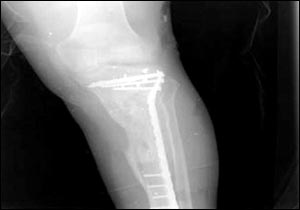

烏代傷腿的X光照片

7月24日,美國國防部通過由美國資助的伊拉克電視臺、兩家阿拉伯衛(wèi)星電視臺以及美國本土的CNN(有線新聞網(wǎng)絡)將薩達姆的兩個兒子烏代和庫賽遭美軍擊斃慘死的照片公諸于世,同時被曝光的還有1996年烏代遇刺后所拍的傷腿的X光片。據(jù)悉,近60的伊拉克人收看這檔節(jié)目。此前,美軍中央司令部的里卡多·桑切斯中將在巴格達舉行新聞發(fā)布會時說,判斷烏代和庫賽被打死的依據(jù)是在現(xiàn)場發(fā)現(xiàn)的牙齒以及曾任薩達姆助手的目擊證人的指認。